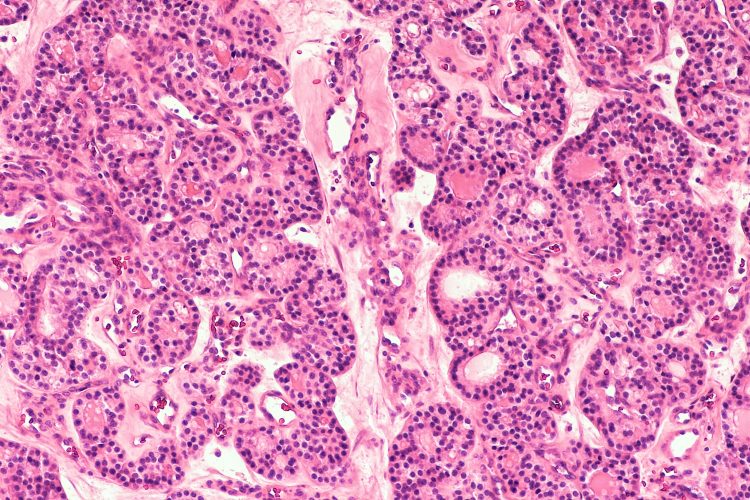

Фотографии опухоли медуллярной аденокарциномы

Раздел: Снимки-откровения